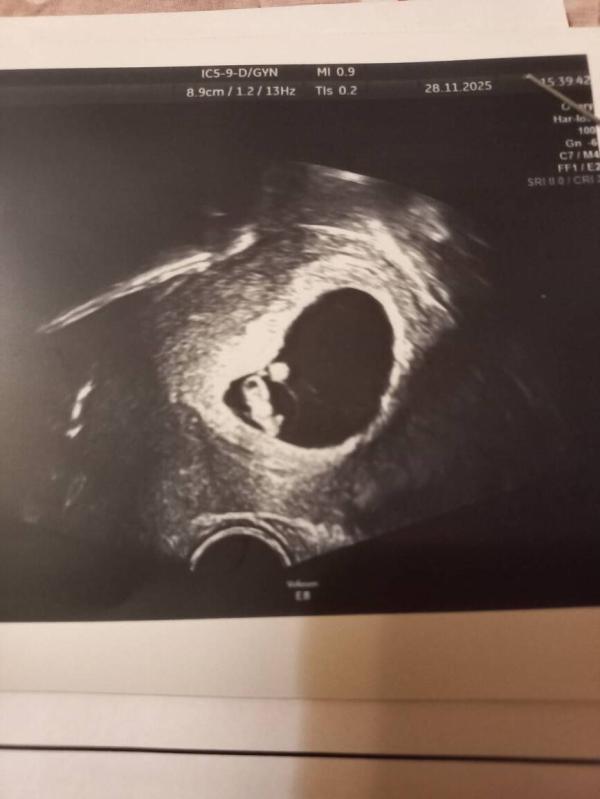

Малявка 13,1 мм, ПЯ 39 мм, ЖМ 13 мм. Надеюсь, все в норме. Срок ставят 6-7 недели, я думала побольше будет, но врач сказала считает от переноса (был 26.10), и по ктр тоже такой срок. На последующих Узи ещё будет уточняться.